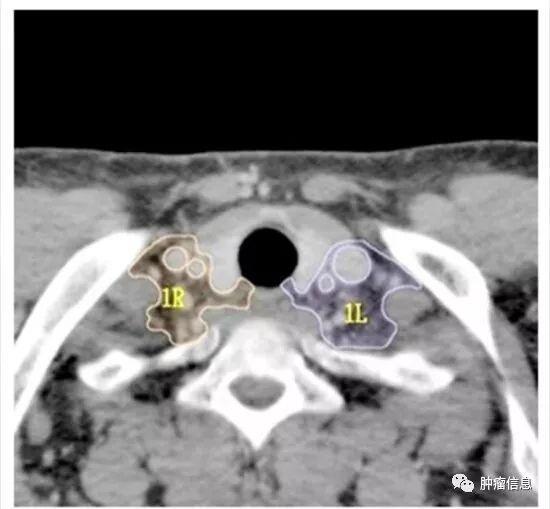

第1组淋巴结

下颈、锁骨上、胸骨切迹淋巴结上界:环状软骨下缘下界:锁骨、胸骨柄上缘气管中线为1L和1R的分界线。